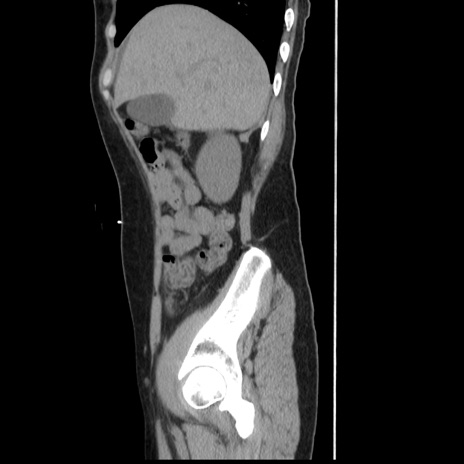

症例10(矢状断像)

【症例】 50歳代女性

【主訴】 腹痛

【現病歴】前日生レバーを食べた。今朝に排便あり。 昼前に突然発症の腹痛を生じ、当院救急外来を受診した。

【既往歴】 子宮筋腫にてで子宮全摘後

【身体所見】 意識清明、腹部:平坦、軟、下腹部やや左を中心に圧痛・反跳痛あり、筋性防御あり

【データ】WBC 7800、CRP 0.07